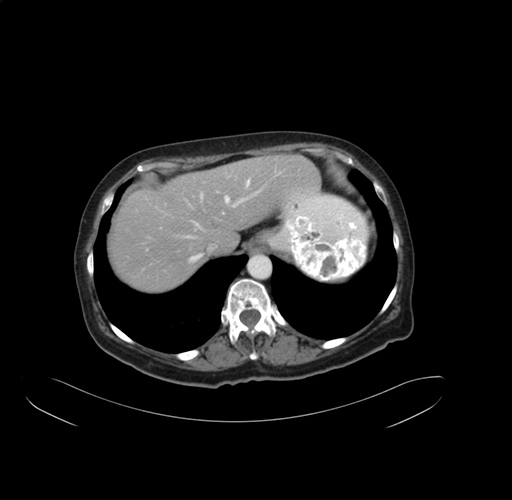

Pre-Chemo: Axial Venous

Axial Venous